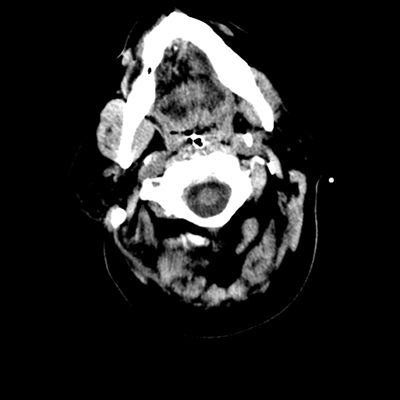

The patient goes down to CT. The following images are obtained. The subdural fluid collection is stable, as is the ventricular caliber.

Starting with the non-contrast head CT, we can appreciate that there's actually not much residual subarachnoid blood at all; it's essentially all resorbed already (and cleared through the EVD). The ventricular caliber is stable. With the CTA head (for convenience's sake, the MIPs were shown), it's subtle, but we can see that the PCAs on each side are not as smooth and regular. The right MCA, starting at the bifurcation, also becomes narrower. This is [radiographic] vasospasm. Now, looking at the CT perfusion-- specifically, the Tmax (MTT) map that were selected-- there's clearly some abnormality within the bilateral cerebellar hemispheres and occipital lobes. Not a lot, but it's there. Delving further into this map, we can appreciate that the areas of abnormality are mainly green, signifying that these areas have Tmax > 6 seconds. This is the threshold that is specific, not sensitive, for vasospasm.

Putting this all together, we have thus identified radiographic vasospasm with the vessel imaging, with perfusion abnormalities that are concordant with it. Does the area of vasospasm and hypoperfusion correlate with the patient's clinical exam?

Yes! It does. The patient had a decline in level of consciousness with diffuse loss of motor function. This does correlate to the basilar territory. (Alternatively, bilateral MCA vasospasm could also be responsible, reminding us that a decline in consciousness could technically be focal/multifocal.) Thus, we can say that this patient does have clinical vasospasm. Whether this will develop into irreversible DCI remains to be seen; at least, the non-contrast head CT and the other portions of the CT perfusion (not shown) currently don't [yet] suggest infarction.